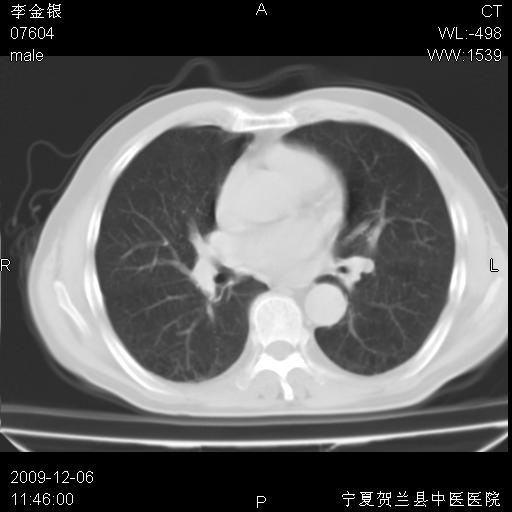

该病人 ,男,62岁,主因咳痰带血两天

考虑右肺中央型占位性病变并阻塞性肺炎.(右肺上叶支气管变窄),建议支纤镜检查.

支持右侧中央型肺癌伴上叶阻塞性炎症.

考虑右肺中心型肺癌伴阻塞性肺炎及右肺门淋巴结转移,建议纤维支气管镜进一步检查。

支气管壁明显增厚 管腔狭窄,腔静脉后多个淋巴肿大,结合年龄病史考虑右肺上叶中央型肺癌并阻塞性肺炎

右肺上叶后段支气管阻塞,右上肺门占位,相应肺段阻塞性肺炎,右肺门有淋巴结肿大。诊断右肺上叶中心型肺癌,阻塞性肺肺炎、右肺门淋巴结转移。

右上叶支气管狭窄,管壁增厚,远端斑片状软组织影,病灶邻近叶间裂,叶间裂无移位。

诊断右肺中央型肺癌。

那个片影应该大部分都是病灶,病灶沿肺段支气管分支生长,后段完全显示不清、闭塞。若为不张应该伴有叶裂的移位,若为炎症应有空气支气管征。